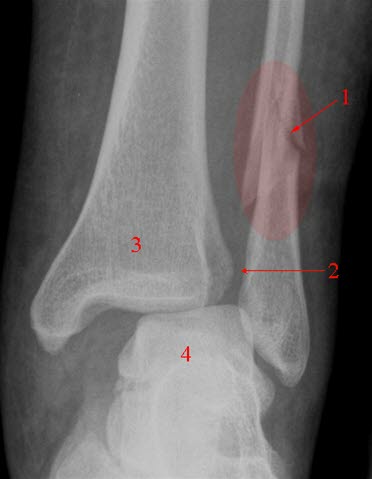

Brudd i ankelen (1)Røntgen av skjelett innebærer undersøkelse av bestemte bein, grupper av bein eller av ledd. Kroppens beinvev har følgende funksjoner:

Ved visse typer skader er det ønskelig å ta såkalte funksjonsbilder, det vil si bilder tatt med leddet i bestemte posisjoner. Slike bilder tas vanligvis ikke i den akutte fasen da smertene vil hindre bevegelsene. Visse typer ankelskader krever f.eks. at man må presse litt på ankelleddet for å få frem forandringer. Nakken må noen ganger avbildes både i fremoverbøyd og bakoverbøyd stilling.